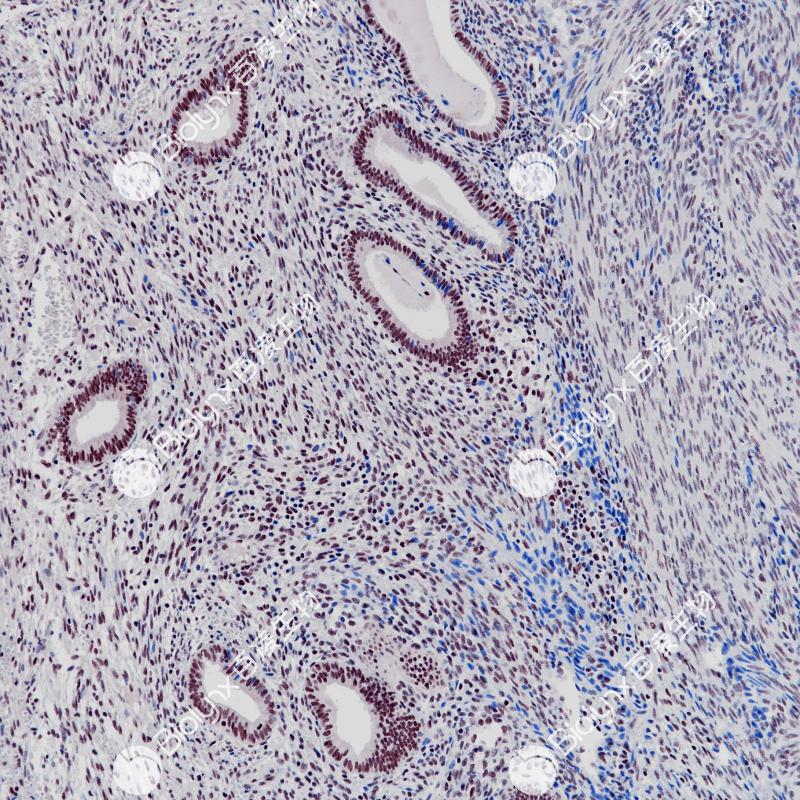

子宫内膜E2F4(BP6256)染色

E2F4是E2F家族中的一种转录因子蛋白,由16号染色体上的E2F4基因编码。E2F家族在控制细胞周期和肿瘤抑制蛋白的作用中起着至关重要的作用,也是小DNA肿瘤病毒转化蛋白的靶点。E2F4在多种肿瘤组织中表达,如乳腺癌、子宫内膜癌、结肠癌等。

阳性对照

子宫内膜癌

亚细胞定位

细胞核